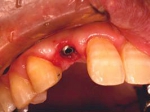

前歯即時埋入症例

術前術前主訴-前歯が腫れて痛い。治療法のうち、ブリッジとインプラントを説明して隣の前歯を削らないですむことからインプラントを選択された。 術前レントゲン術前レントゲン術前レントゲン 抜歯抜歯抜歯を行う。折れていた位置がかなり深い位置であるのがわかる。 歯根も抜歯歯根も抜歯

歯根も抜歯歯根も抜歯歯根も抜歯 抜歯した穴をよく掃除抜歯した穴をよく掃除抜歯した穴をよく掃除(掻爬)後すぐにインプラントを埋入 埋入直後のレントゲン埋入直後のレントゲン埋入直後のレントゲン。上部に見えるのは抜いた歯を利用して両どなりの歯に接着して一時的に使えるようにした。 二次オペ時二次オペ時

仮の支柱を装着仮の支柱を装着仮の支柱を装着 作業模型上のセラミック上部構造作業模型上のセラミック上部構造作業模型上のセラミック上部構造 術後術後術後